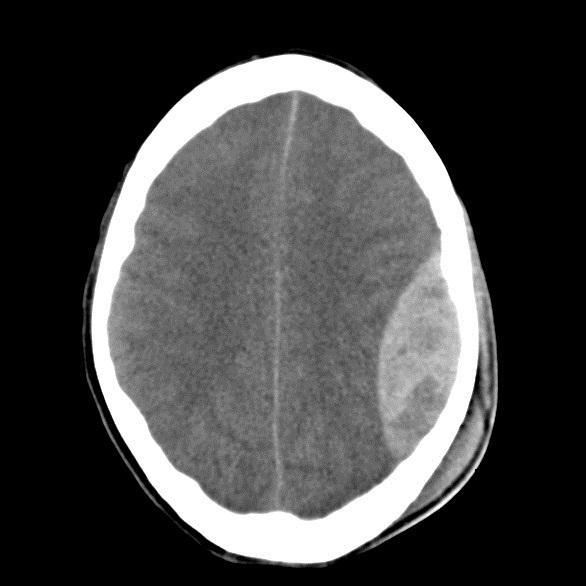

Extradural Haem

Il y a 7 ans